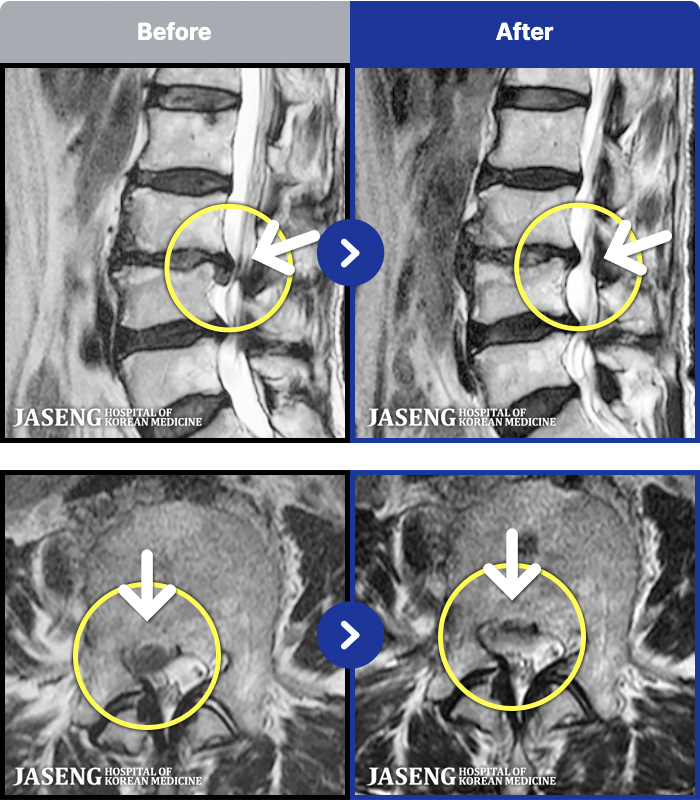

MRI ġ

1,245 MRI ũ ʸ Ȯϼ.